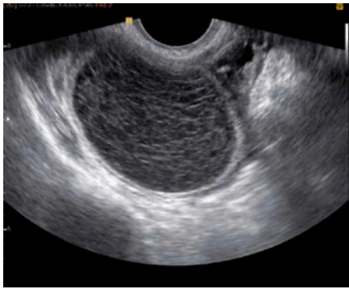

Paciente de 24 anos, comparece ao pronto socorro com queixa de dor em região suprapúbica e na fossa ilíaca à direita, com início há cerca de 2 dias e piora progressiva. Nega queixas urinárias ou gastrointestinais. Menarca aos 12 anos, sexarca aos 18 anos, vida sexual ativa com parceiro único, com uso de preservativo masculino. Método contraceptivo: DIU de cobre. A data da última menstruação foi há 2 semanas e 5 dias. Ao exame físico, bom estado geral, estável hemodinamicamente, mucosas coradas; dor à palpação profunda da fossa ilíaca direita, sem sinais de peritonite. Ao toque vaginal, identifica-se massa palpável na mesma topografia.

A USG-TV veio com o seguinte achado:

Frente a essas informações, qual a melhor hipótese diagnóstica?